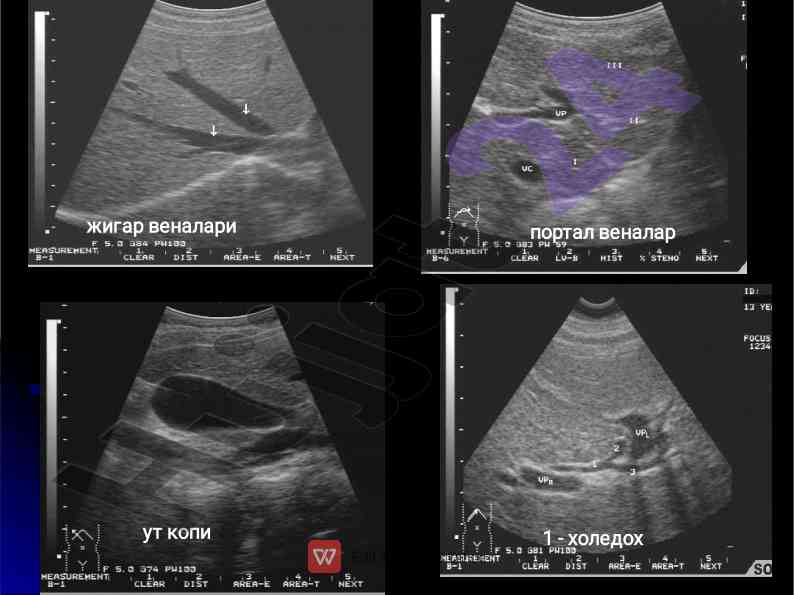

Jigar kasalliklari nur tashxisi va tashxis metodlari

Jigar kasalliklari uchun nur tashxisi va zamonaviy usullarni, shu jumladan kompyuter tomografiya va doppler tadqiqotlari haqida ma'lumot.